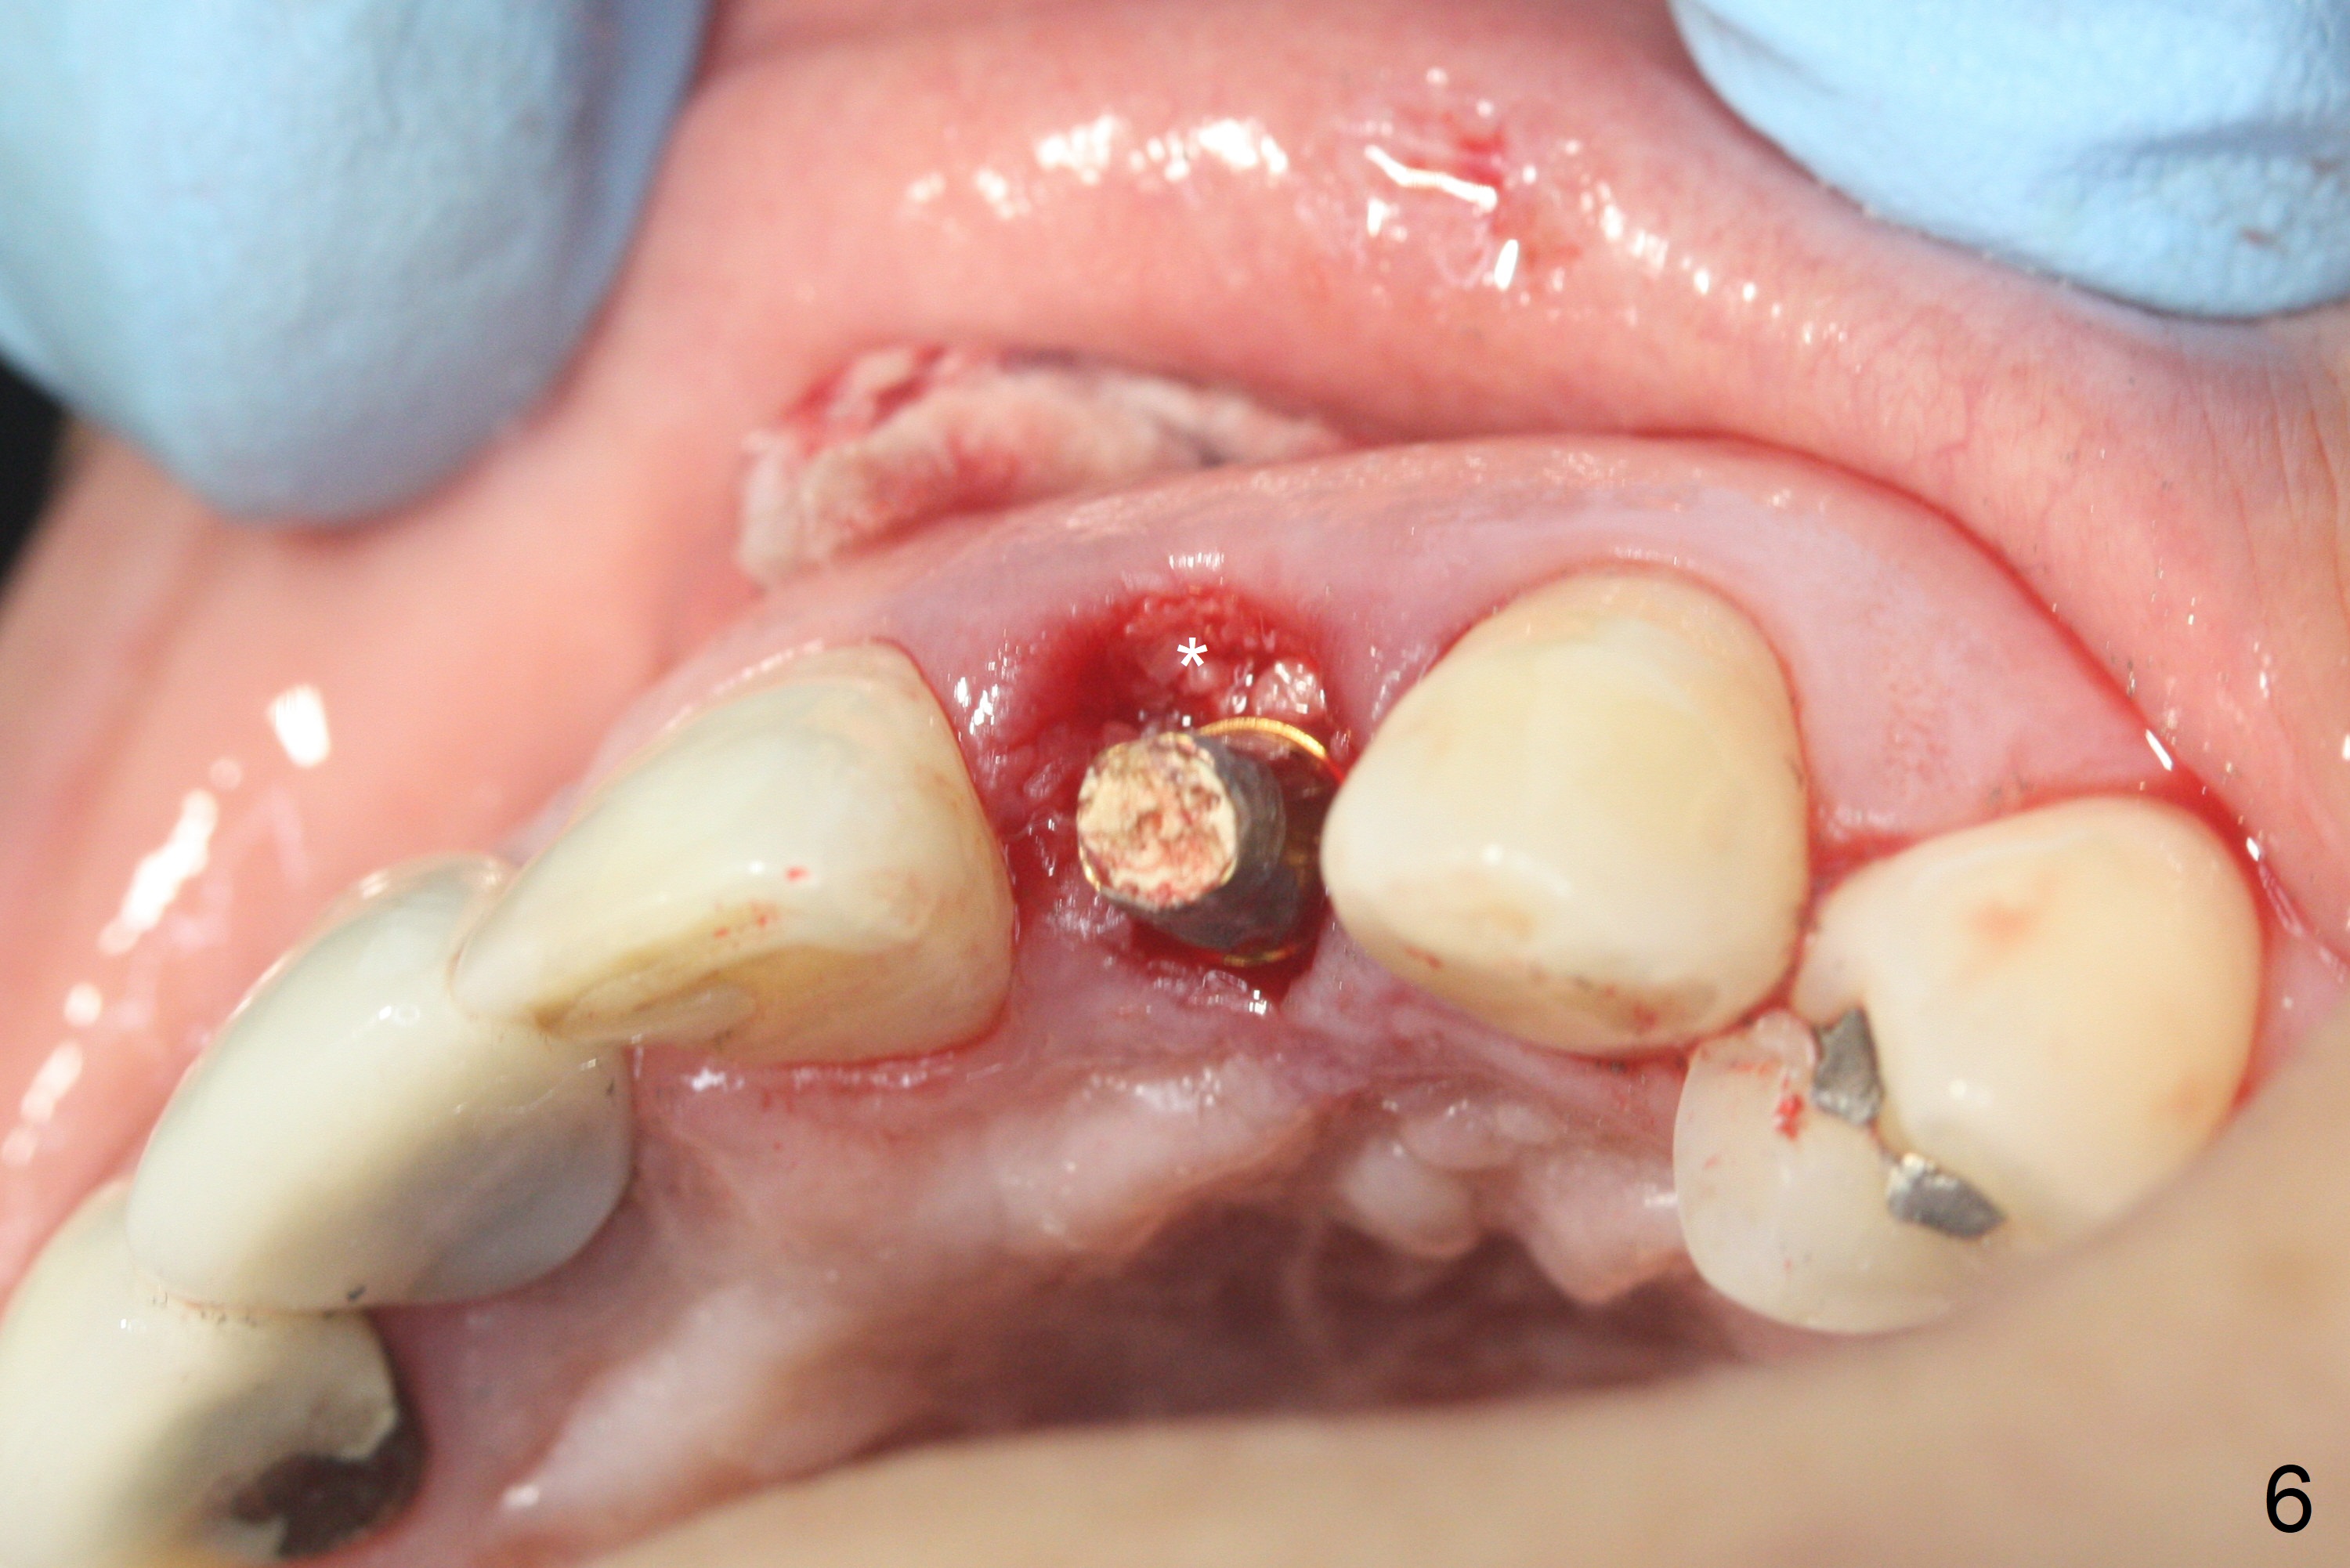

When the patient returns, the crown at #10 has displaced incisally (Fig.1,2 arrow). The initial depth is 15 mm (Fig.3, palatal gingival margin). After a 3.8x12 mm SM implant is placed (Fig.4), allograft is packed in the peri-implant space (*, as compared to Fig.3) and a 3.9x4(3) mm abutment is placed (A). More allograft is placed in the peri-abutment space (Fig.6 *). The existing crown (Fig.4,5 C) is hollowed, relined (R) and used as an immediate provisional (Fig.7-9). The patient is pleased with the appearance of the apically-repositioned provisional (Fig.7 arrow). She returns for impression 3.5 months postop (Fig.10). After change of abutment to 3.9x4(4.5) mm and new provisional, impression is retaken 5 months postop (Fig.11,12). It appears that the implant is palatally placed and a little large for the site (Fig.11 (B: buccal); Fig.12 (^: thin layer of the palatal plate)). If an angled abutment were used, a screw-retained crown might have been feasible. Due to the new provisional, the gingiva looks healthy when a permanent crown is cemented (Fig.13).